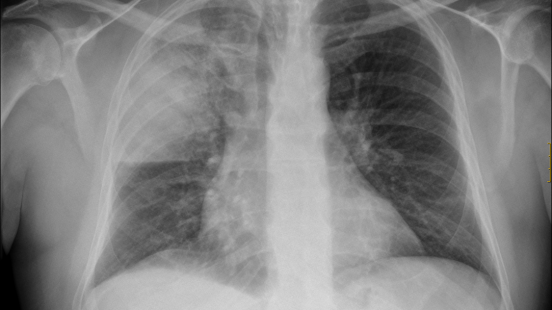

Los facultativos se han dado cuenta de que muchos de los enfermos que derivan en neumonía bilateral no advirtieron tener problemas respiratorios, aunque sus radiografías de tórax mostraron una neumonía difusa y sus niveles de oxígeno estaban por debajo de lo normal.